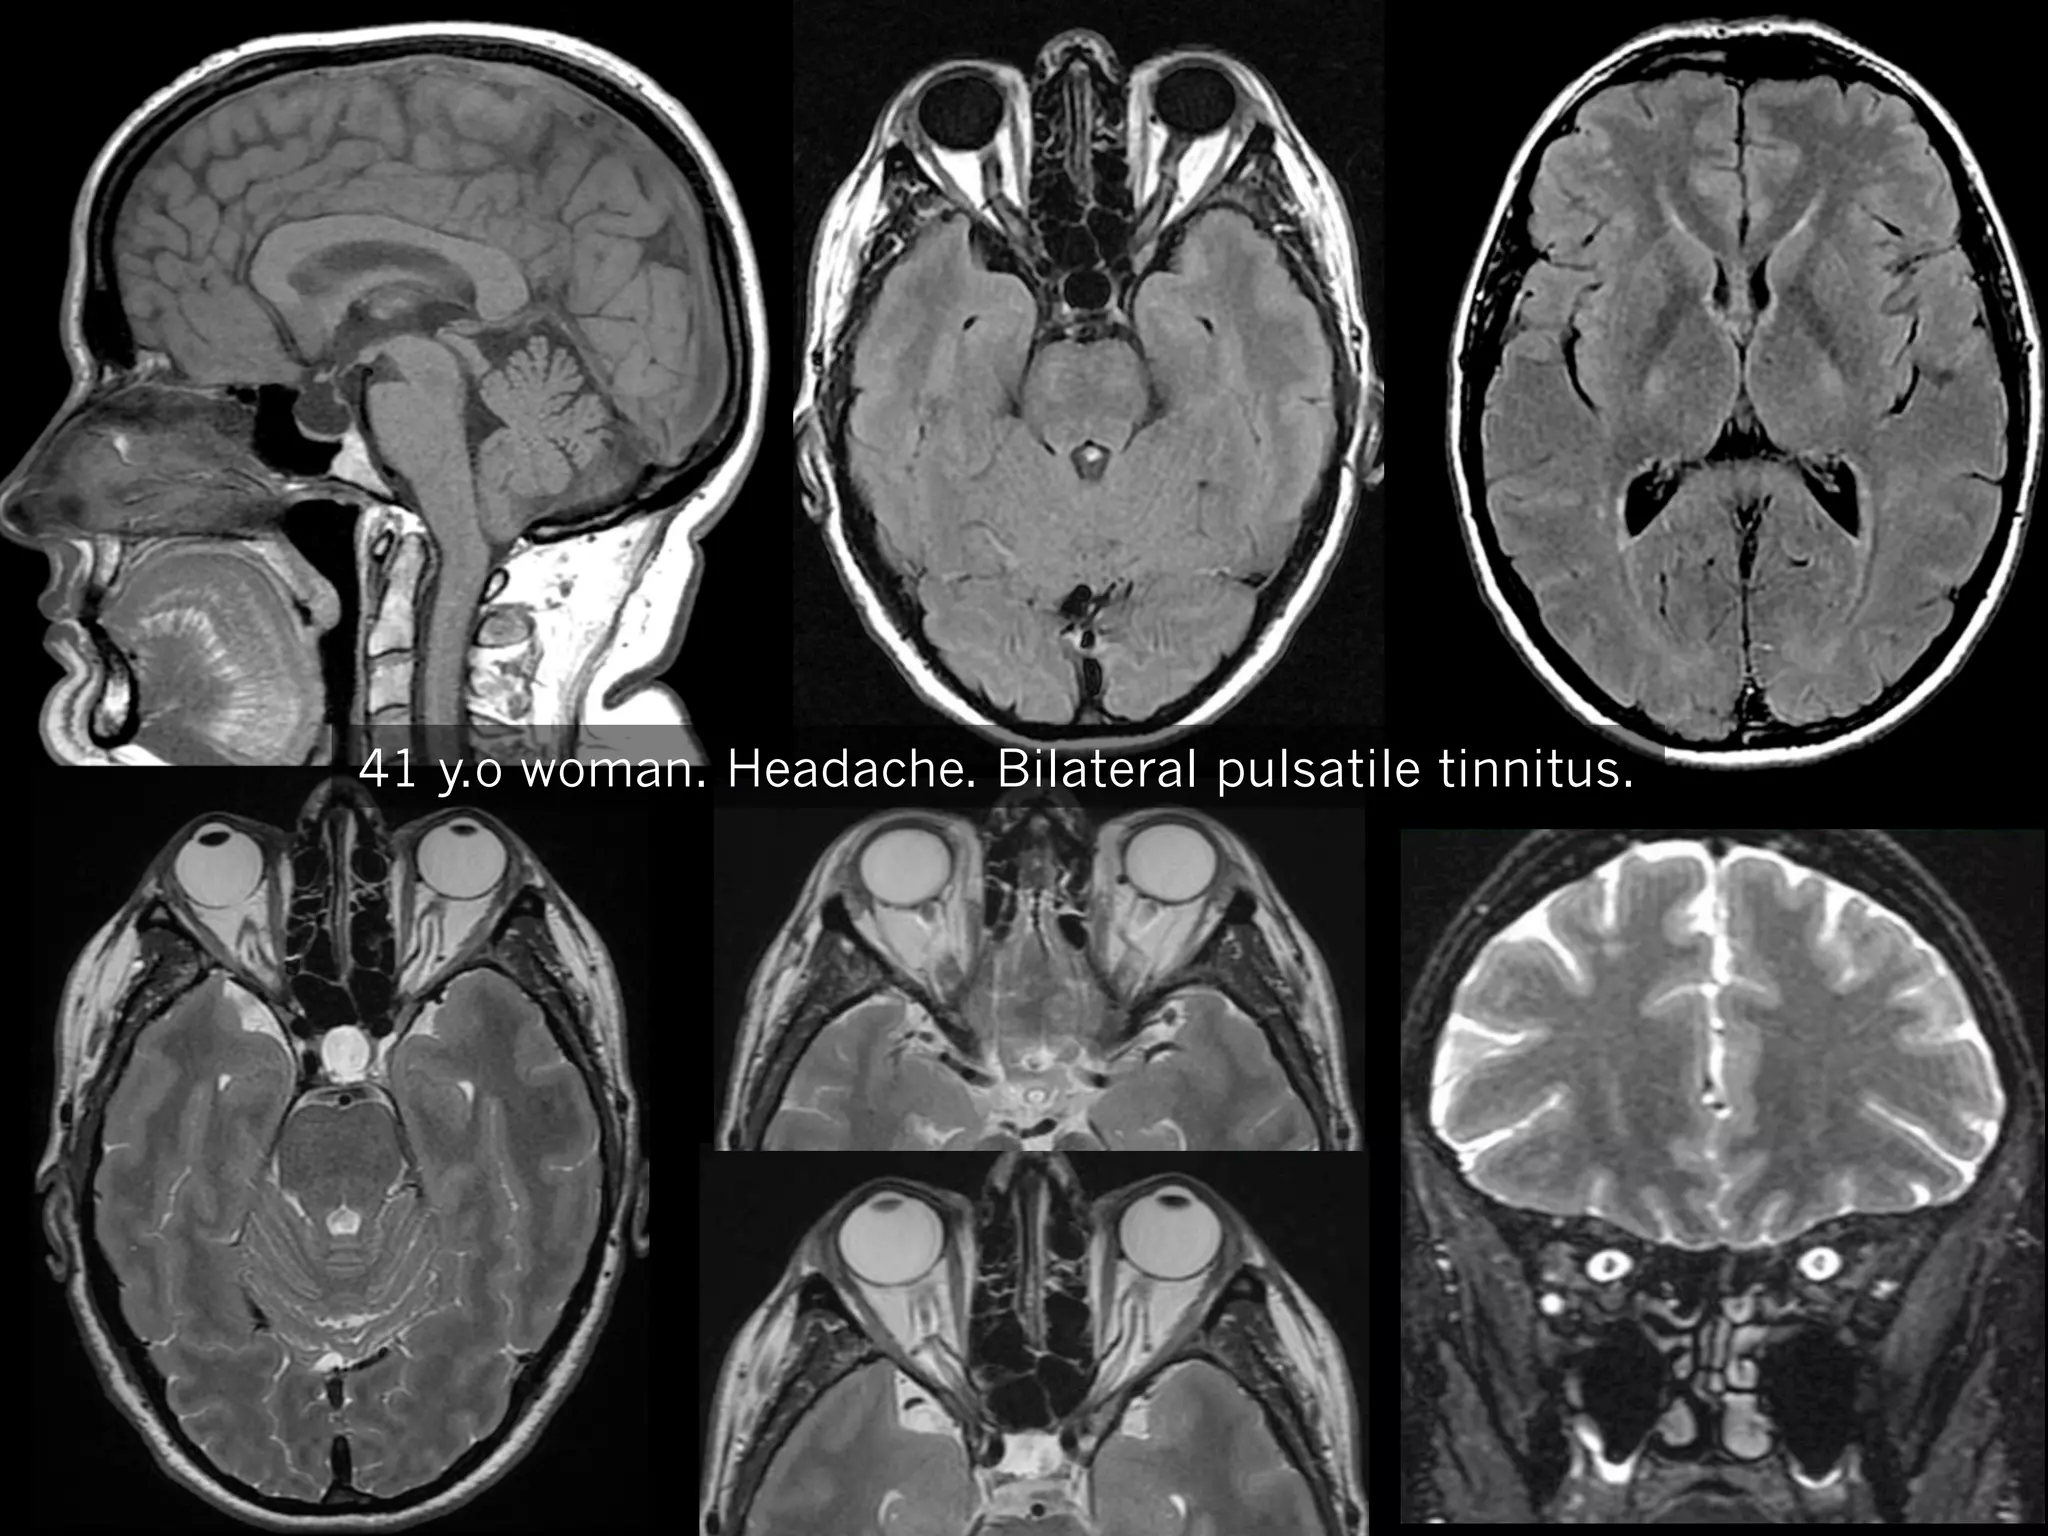

41 y.o woman. Headache. Bilateral pulsatile tinnitus.

Enlargement

of

peri optic sub archnoid spaces

Tortuous optic nerves